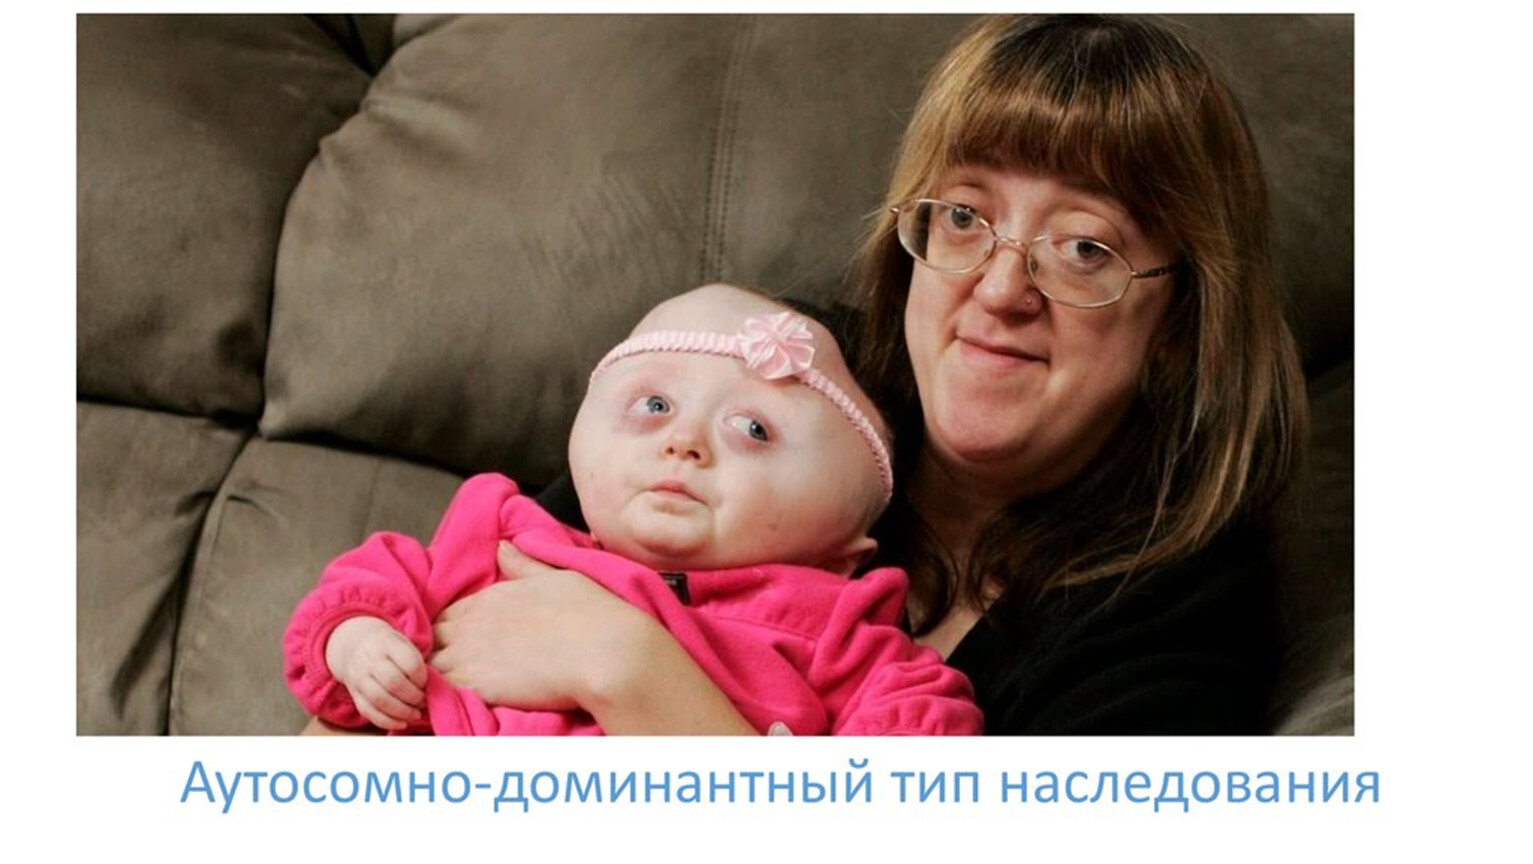

Ларсена йохансона

Ларсена йохансона 146 фото